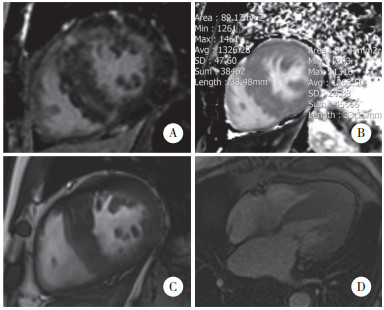

由放射科1名主治医师及1名副主任医师共同测量并评估。(1) 累及心内膜下的LGE:无心肌梗死证据的患者累及心内膜下的LGE与冠状动脉血管分布不相对应,可同时累及其他层面心肌,表现为心内膜下斑片状强化、边界模糊。(2) 右心室插入部LGE:室间隔和右心室游离壁连接处的LGE。(3) 左心室LGE心肌及计数:根据16分段法对左心室心肌进行分段,记录LGE左心室节段,并对每位患者左心室LGE心肌节段计数求和。(4) 伴LGE左心室心肌初始T1 mapping值:对比LGE图像,在对应T1 mapping图像心肌节段(心内外膜间) 画取感兴趣区(region of interest,ROI) 测量3次,结果取平均值。(5) 无LGE左心室心肌初始T1 mapping值:对比LGE图像,在无LGE对应T1 mapping图像心肌节段(心内外膜间) 画取感兴趣区,测量3次,结果取平均值。(6) 左心室最大厚度、左心室最大横径:于短轴舒张末期测量。(7) 左心房前后径:于四腔心层面测量。(8) 左心室流出道梗阻:超声心动图瞬时峰压差值≥30 mmHg。见图 1。

| A,the short-axis view of LGE image;B,the short-axis view of native T1 mapping image;C,short-axis diastole cines;D,4-chamber view of first-pass perfusion,no perfusion defect signal was found in the left ventricle subendocardial. 图 1 HCM并发AF患者CMR图像分析 Fig.1 CMR image analysis of HCM with AF |